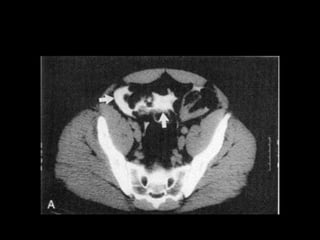

Diagnostico

• Estudio elección: cistograma de llenado 350-

400ml solución salina, con 4% de contraste a

• Cystography: Gold standard

• CT Cystography : New trend

• Peng et al. AJR 2011.

– Prospective study

– 305 patients.

– Cystography VS. CT cystography

– Ruptures confirmed by Surgery

– 100% sensitive and specific